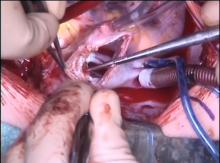

The authors present a case of 6-year-old child with an anomalous venous drainage from the superior and medial lung lobes to the superior vena cava, associated with a large ASD. This video demonstrates the authors’ preferred technique for repairing these congenital defects, using the warden technique. The authors believe that the warden technique is a safe and reproducible way to correct almost every case of anomalous drainage. In the long term, this type of repair may protect from rhythm disturbances and from venous pathway obstruction.